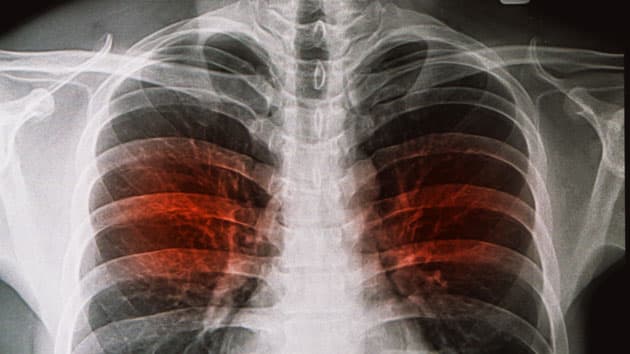

Kortere antibiotisk behandling for stabil, ukompliceret lungebetændelse